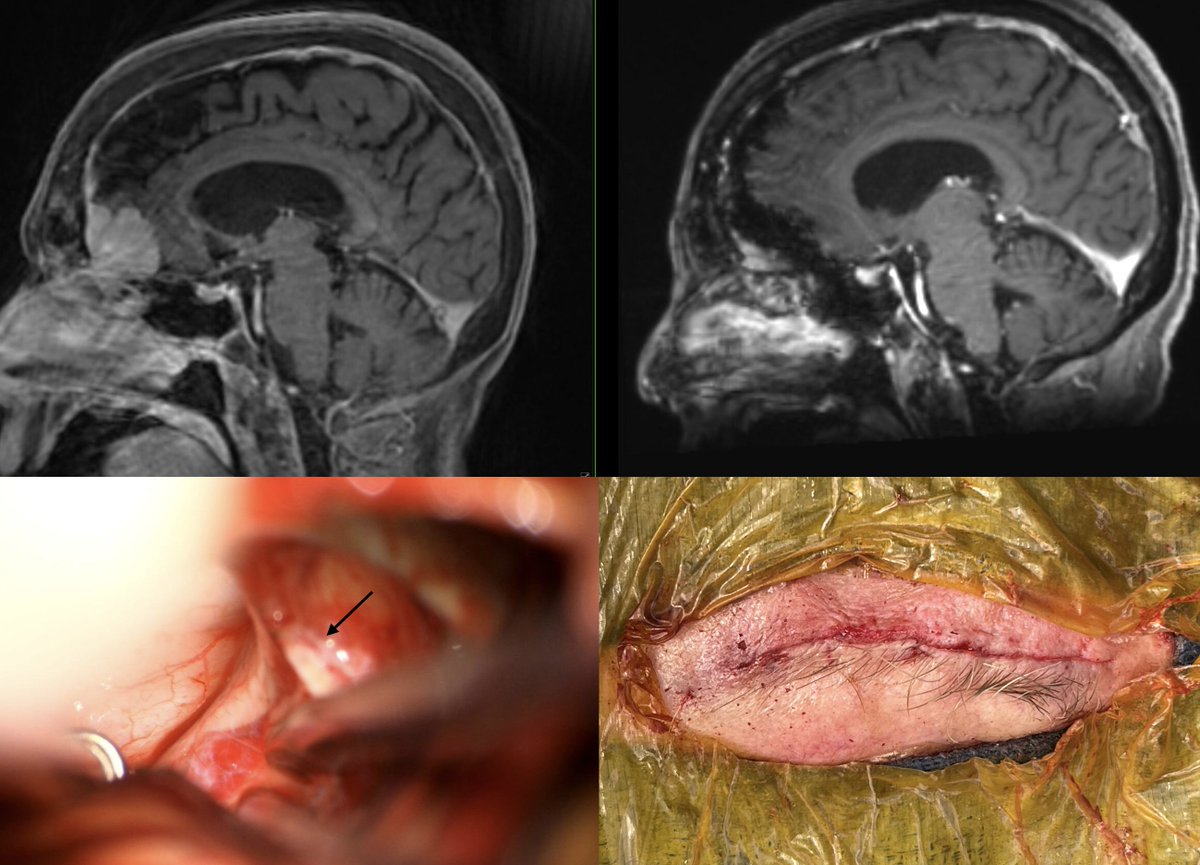

بحمد الله وتوفيقه ثم ببركة دعاء الوالدين، أنهيت زمالة التخصص الدقيق في جراحة الأورام العصبية من مركز Cedars-Sinai Academic Medicine. كل الشكر والتقدير لجميع أعضاء الفريق الطبي من جرّاحين وتمريض وفنيين. كما أخص بالشكر مدير برنامج الزمالة John Yu على كل ما تعلمته منه داخل وخارج غرف العمليات.